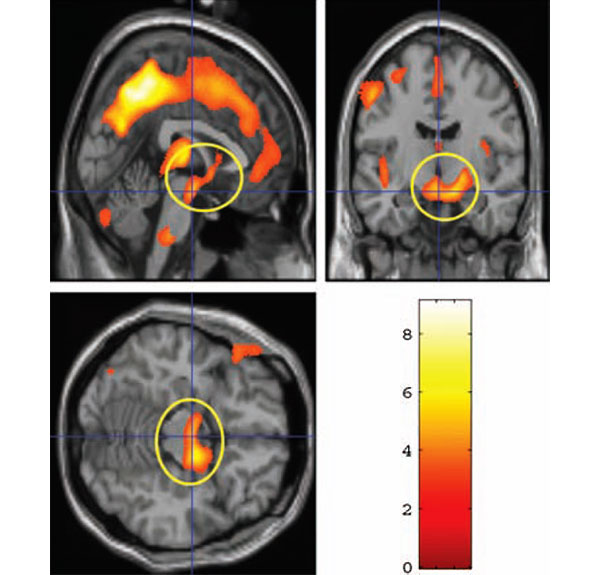

Каждой участнице просканировали мозг при помощи фМРТ дважды: первый раз спустя 2–4 недели после родов, второй — через 3–4 месяца. Полученные трехмерные изображения затем обрабатывались специальными программами, позволяющими измерить объем серого вещества в тех или иных отделах мозга (см.: Statistical parametric mapping, SPM).

В промежутке между первым и вторым сканированием у женщин достоверно увеличился объем серого вещества во многих областях префронтальной и теменной коры, в таламусе, гипоталамусе, миндалине, черном веществе (substantia nigra) и других отделах, связанных с эмоциональной регуляцией поведения.

Оказалось, что количество восторженных эпитетов, которыми мать наградила своего малыша во время тестирования через 2–4 недели после родов, является хорошим предиктором роста серого вещества в гипоталамусе, миндалине и substantia nigra в последующие 2–3 месяца: кто выбрал больше эпитетов, у того и прибавилось больше серого вещества в этих отделах. Степень восторженности по отношению к материнству, однако, не коррелирует с ростом серого вещества.